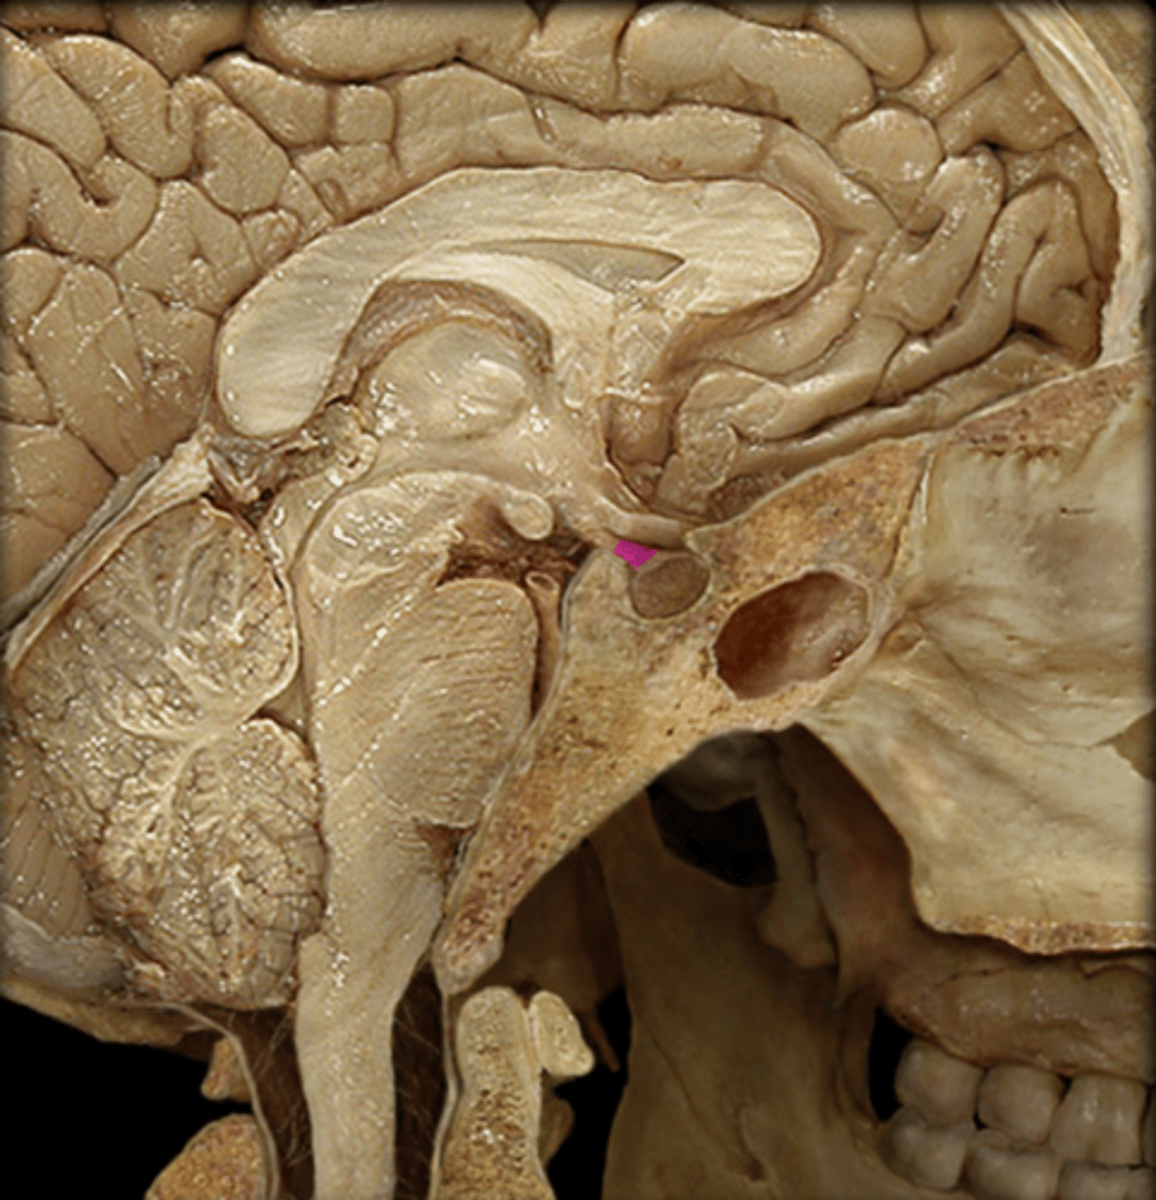

Hypothalamus and Pineal Gland Anatomy & Physiology II Lab (Hypothalamus & Pineal Gland: Dissection & Notes) Endocrine System

pineal gland

What hormone is produced in the pineal gland?

melatonin

Hormone of the Pineal Gland

Makes us drowsy and regulates our sleep-awake cycle called the circadian rhythm. Production increases during periods of darkness and decreases with increased light.

epithalamus

The pineal gland is located in the ________________.

pineal sand

The pineal gland has an important role in radiology due to the presence of a radioplaque substance called ____________ ____________. This provides radiologists with an easily distinguished landmark.